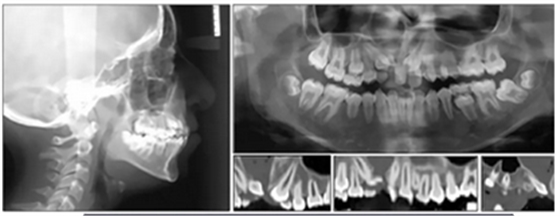

全景片示:側(cè)切牙扭轉(zhuǎn)、發(fā)育異常,影響上頜左側(cè)尖牙,下頜左側(cè)第二磨牙嚴(yán)重近中傾斜。幾乎所有的牙齒都是短根,但沒有觀察到牙根吸收的現(xiàn)象。

頭部側(cè)位片測量顯示骨性I類錯合畸形(ANB,3.5°),垂直生長模式(SN / GoMe,39°),上頜中切牙后傾(1 / SN,94°)和下頜中切牙前傾(IMPA,100 °)(圖3)。